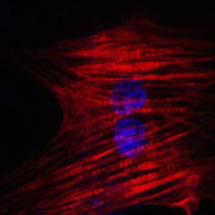

Célula del corazón reprogramada a partir de una célula de la piel. Imagen: Nan Cao. Fuente: Institutos Gladstone.

En el estudio de Science, dirigido por el primer autor Nan Cao, postdoc en el laboratorio de Ding, los investigadores utilizaron un cóctel de nueve productos químicos para transformar las células de piel humana en células del corazón. Por ensayo y error, encontraron la mejor combinación de productos químicos para comenzar el proceso, cambiando las células a un estado parecido al de las células madre multipotentes, que pueden convertirse en muchos tipos diferentes de células en un órgano en particular.

Un segundo cóctel de sustancias químicas y factores de crecimiento ayudó a las células a convertirse en células musculares del corazón.

Con este método, más de 97% de las células comenzaron a latir, una característica de las células del corazón completamente desarrolladas y sanas. Las células también respondieron apropiadamente a las hormonas, y molecularmente, se parecían a las células del músculo del corazón, no a las células de la piel. Es más, cuando las células fueron trasplantadas a un corazón de ratón al inicio del proceso, evolucionaron a células musculares del corazón de aspecto saludable.

"El objetivo final de tratar la insuficiencia cardíaca es conseguir una manera robusta y fiable de que el corazón cree nuevas células musculares", dice Srivastava, co-autor principal del artículo de Science. "La reprogramación de células del propio paciente podría ser la forma más segura y eficiente de regenerar músculo cardíaco enfermo o agonizante."

En el estudio de Science, dirigido por el primer autor Nan Cao, postdoc en el laboratorio de Ding, los investigadores utilizaron un cóctel de nueve productos químicos para transformar las células de piel humana en células del corazón. Por ensayo y error, encontraron la mejor combinación de productos químicos para comenzar el proceso, cambiando las células a un estado parecido al de las células madre multipotentes, que pueden convertirse en muchos tipos diferentes de células en un órgano en particular.

Un segundo cóctel de sustancias químicas y factores de crecimiento ayudó a las células a convertirse en células musculares del corazón.

Con este método, más de 97% de las células comenzaron a latir, una característica de las células del corazón completamente desarrolladas y sanas. Las células también respondieron apropiadamente a las hormonas, y molecularmente, se parecían a las células del músculo del corazón, no a las células de la piel. Es más, cuando las células fueron trasplantadas a un corazón de ratón al inicio del proceso, evolucionaron a células musculares del corazón de aspecto saludable.

"El objetivo final de tratar la insuficiencia cardíaca es conseguir una manera robusta y fiable de que el corazón cree nuevas células musculares", dice Srivastava, co-autor principal del artículo de Science. "La reprogramación de células del propio paciente podría ser la forma más segura y eficiente de regenerar músculo cardíaco enfermo o agonizante."